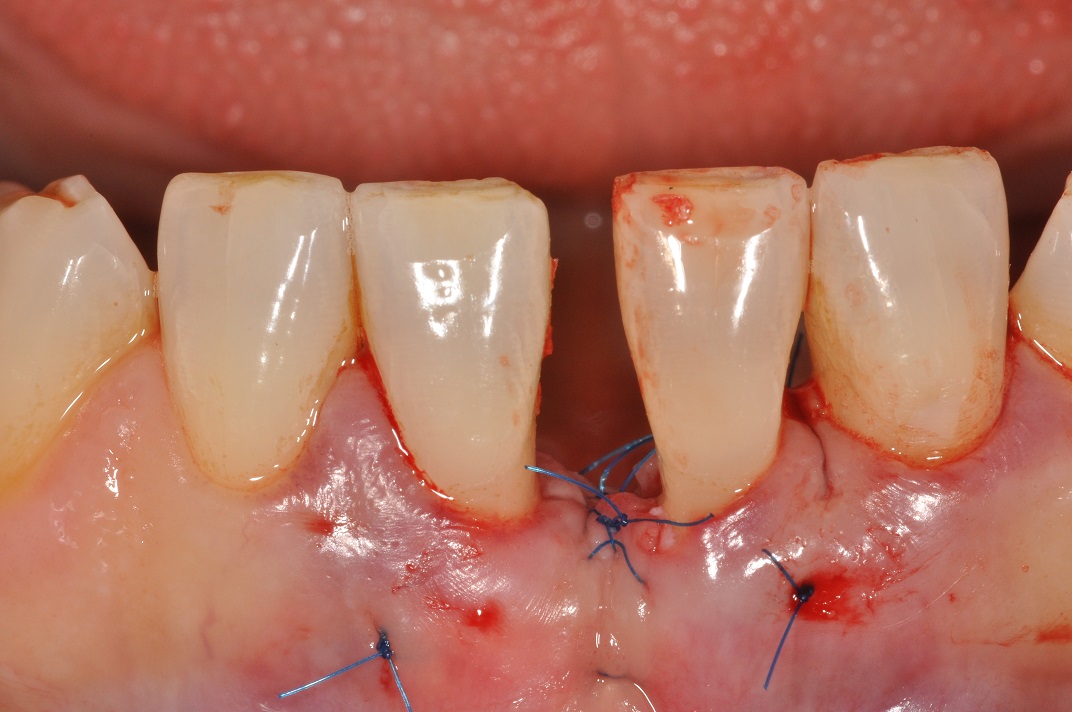

07/13 - Suturing.

Wide intrabony defect treated with the modified papilla preservation flap in conjunction with Straumann® Emdogain® and autogenous bone - Dr. B. Molnar